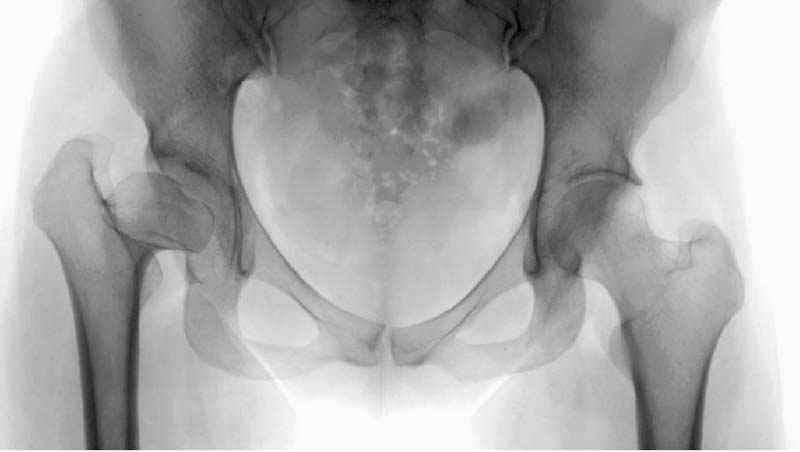

До операции #1

№ 1-3 до операции